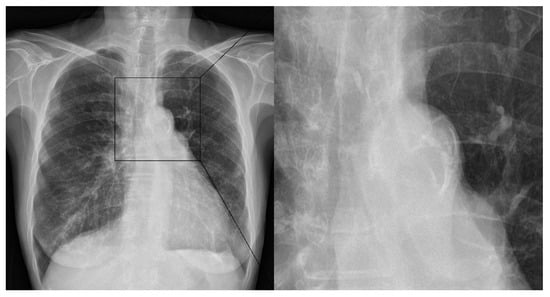

- Kim, H.G.; Lee, S.H.; Nam, T.M.; Jang, J.H.; Kim, Y.Z.; Kim, K.H.; Kim, D.H.; Kim, S.H. Association of Aortic Arch Calcification on Chest X-ray with Procedural Thromboembolism after Mechanical Thrombectomy for Acute Ischemic Stroke. Medicina 2021, 57, 859. [Google Scholar] [CrossRef]

- Kim, S.H.; Nam, T.M.; Lee, S.H.; Jang, J.H.; Kim, Y.Z.; Kim, K.H.; Kim, D.H.; Lee, C.H. Association of aortic arch calcification on chest X-ray with procedural thromboembolism after coil embolization of cerebral aneurysm. J. Clin. Neurosci. 2022, 99, 373–378. [Google Scholar] [CrossRef] [PubMed]